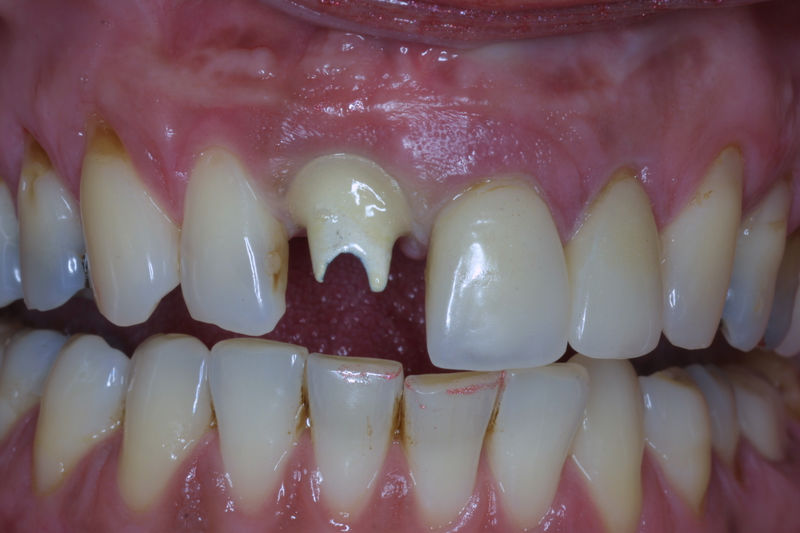

La restauración de un diente tras una endodoncia, es crucial para su supervivencia a largo plazo, ya que el procedimiento puede debilitar la estructura dental. El tipo de restauración elegido depende principalmente de la cantidad de estructura dental remanente después de la endodoncia. Principalmente se usan incrustaciones, coronas y/o postes.

Son aditamentos artificiales colocados en la parte interna de la raíz de dientes con tratamiento endodóntico y con amplia destrucción. Usados comúnmente para soportar coronas completas.

Implante fracasado, extracción, carillas, coronas y prótesis fija.